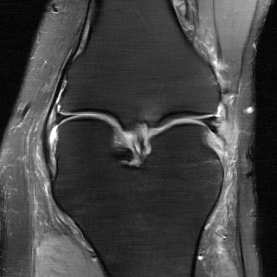

Deep Learning (DL) methods have shown promising results for solving ill-posed inverse problems such as MR image reconstruction from undersampled $k$-space data. However, these approaches currently have no guarantees for reconstruction quality and the reliability of such algorithms is only poorly understood. Adversarial attacks offer a valuable tool to understand possible failure modes and worst case performance of DL-based reconstruction algorithms. In this paper we describe adversarial attacks on multi-coil $k$-space measurements and evaluate them on the recently proposed E2E-VarNet and a simpler UNet-based model. In contrast to prior work, the attacks are targeted to specifically alter diagnostically relevant regions. Using two realistic attack models (adversarial $k$-space noise and adversarial rotations) we are able to show that current state-of-the-art DL-based reconstruction algorithms are indeed sensitive to such perturbations to a degree where relevant diagnostic information may be lost. Surprisingly, in our experiments the UNet and the more sophisticated E2E-VarNet were similarly sensitive to such attacks. Our findings add further to the evidence that caution must be exercised as DL-based methods move closer to clinical practice.